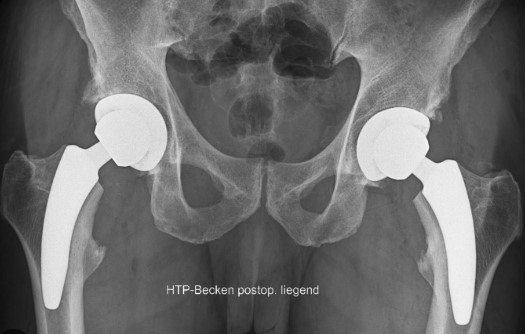

Hüft TEP beidseits mittels Kurzschaftprothese, zementfrei